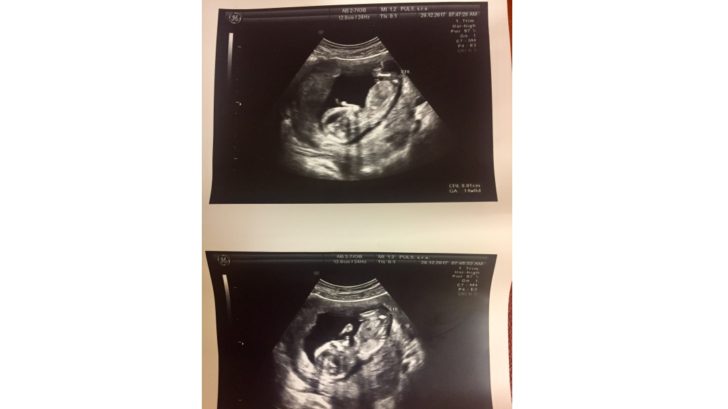

Omlouvám se, jestli jsem vás, čtenářky zklamala, asi jste čekaly další klasický těhu-mama text. Nejsem úplně typická těhotná, ale slibuji, že v dalším příspěvku si i vy přijdete na své. Zavzpomínám na Vánoce, první velký ultrazvuk, naťuknu téma pohlaví a jména miminka, prozradím, jestli už se změnil můj šatník, jak o sebe pečuji a jestli se nějak speciálně stravuji. Ale o pohybu to bude zase taky. A nejen o mém! Náš Sebík za mnou totiž nezaostává…